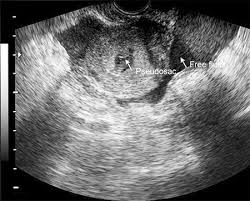

It’s important to understand that fluid in the cul-de-sac during early pregnancy doesn’t automatically mean an ectopic pregnancy. While it can be a sign, other factors need to be considered. For example, hCG levels that aren’t rising as expected and an ultrasound that can’t pinpoint the pregnancy location might point towards an ectopic pregnancy. In such cases, procedures like dilation and curettage (D&C) or manual vacuum aspiration (MVA) might be recommended. These procedures can help determine if a gestational sac or chorionic villi are present, which can offer more definitive information.

However, cul-de-sac fluid can also occur due to other reasons, such as a normal pregnancy or fluid buildup from a prior surgery. Therefore, it’s crucial to consult with a healthcare professional who can assess your specific situation. They will consider all factors, including your medical history, symptoms, and test results, to arrive at an accurate diagnosis and guide your care.

While fluid in the cul-de-sac can sometimes be a sign of an ectopic pregnancy, it’s not always the case. The cul-de-sac is a small pouch located behind the uterus. It’s normal to have a small amount of fluid in the cul-de-sac, especially after your period. During early pregnancy, this fluid can sometimes increase due to hormonal changes, blood flow, and the growing uterus.

However, if the amount of cul-de-sac fluid is significant, or if it’s accompanied by other symptoms like pain, bleeding, or fever, it’s important to consult a doctor. These symptoms could indicate a more serious condition, such as an ectopic pregnancy.

It’s crucial to remember that an ectopic pregnancy occurs when a fertilized egg implants outside the uterus, typically in the fallopian tube. This is a serious medical condition that requires immediate attention. If you’re experiencing any of these symptoms, seek medical care immediately.

A doctor will perform a thorough evaluation, which may include a pelvic exam, ultrasound, and blood tests. Based on the results, they will determine the cause of the cul-de-sac fluid and recommend the appropriate treatment plan. Remember, early detection and prompt treatment are crucial for achieving the best outcome.